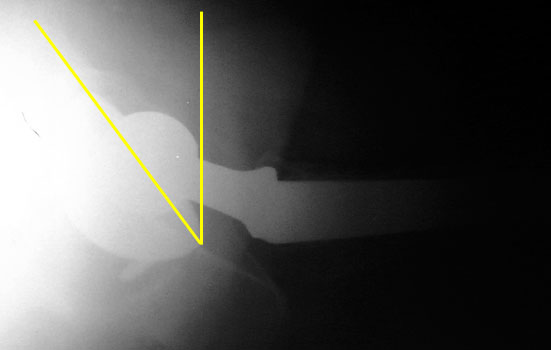

Groin lateral films: R cup normal anteversion, L cup excessive anteversion

Femoral component should be anteverted. Exact degree of optimal anteversion is unknown

Femoral neck anteversion is difficult to accurately evaluate on radiographs, and can only be qualitatively assessed on a groin lateral view. This view is difficult to obtain, especially in the elderly or post operative patient, and is effected by pelvic or thigh rotation.

CT is the imaging modality of choice to evaluate for femoral neck anteversion.

Femoral neck anteversion on groin lateral film.

Version of acetabular and femoral components may be cumulative. Therefore, a retroverted cup can be compensated by an anteverted femoral component